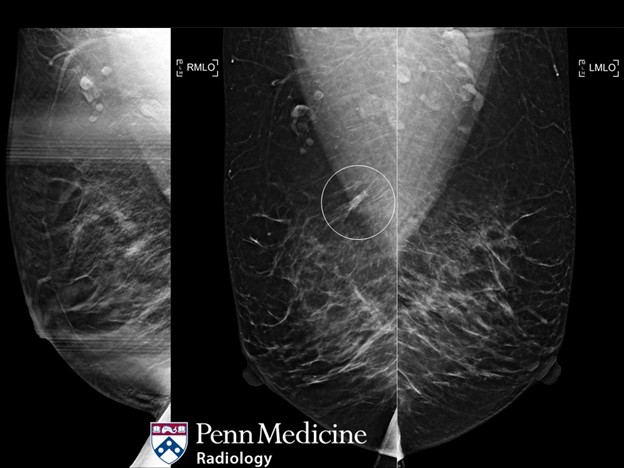

Cases of the Week

Check out our Cases of the Week!